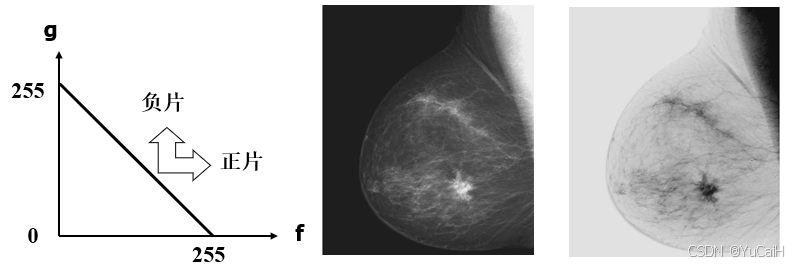

灰度反转

黑白图像的反转就是使灰度值为 1 的像素值变成 0 ,使灰度值为 0 的像素值变成 1

对于256灰度级图像来说,图像的灰度反转值就是用 255 分别减去原图像的各个像素的灰度值

设图像的灰度级为L,则图像的灰度反转可表示为:

g ( x , y ) = L − 1 − f ( x , y ) g(x,y) = L-1-f(x,y) g(x,y)=L−1−f(x,y)